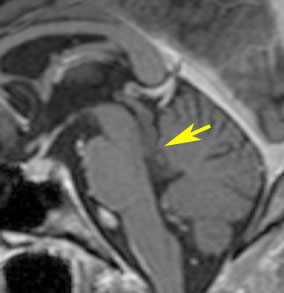

左はT2強調画像,右はFLAIR画像です。中脳視蓋 tectum の中でも上丘が腫瘍化していることが解りますし,松果体は正常の大きさで腫瘍の上に乗っていますから,松果体腫瘍ではないことが解ります。上髄帆にも浸潤しています。